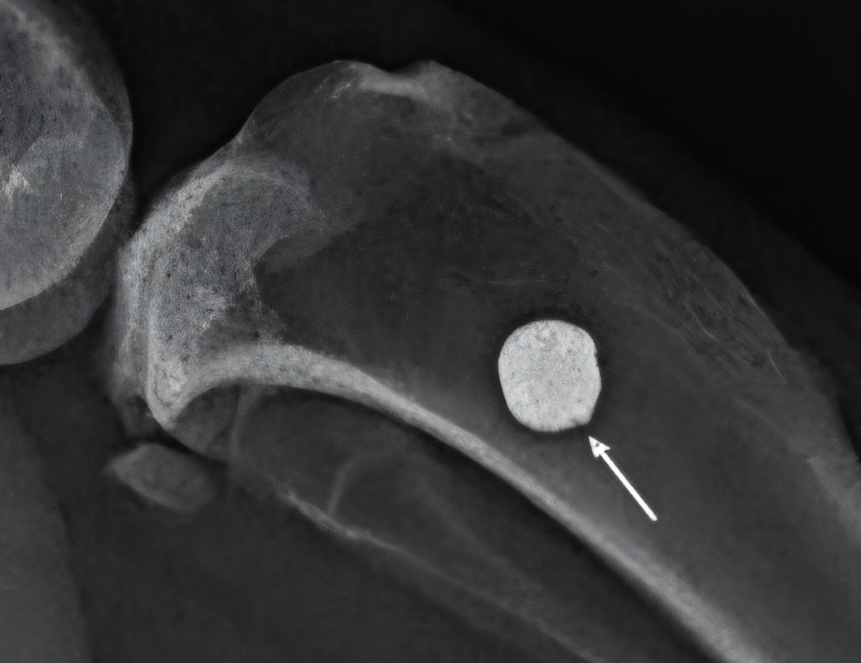

Рентгенограмма имплантатов в области операции через три месяца эксперимента. Источник: Елена Ермакова / ИМЕТ РАН.

Ученые из Института металлургии и материаловедения имени А.А. Байкова РАН (Москва) и Национального медицинского исследовательского центра травматологии и ортопедии имени академика Г.А. Илизарова (Курган) обнаружили, что не все часто используемые в имплантатах редкоземельные металлы и их примеси безопасны для живых существ. Авторы провели исследование на 46 самцах крыс, которых разделили на четыре группы. Первой под кожу ввели титановый имплантат с добавлением иттрия, второй — с лантаном, третьей — с церием, а четвертой (контрольной) поместили чистый титановый имплантат. В течение следующих четырех недель исследователи оценивали общее состояние здоровья животных, массу, температуру их тела и локальную температуру в месте установки имплантата.

Через три месяца после операции ученые исследовали кровь крыс. У грызунов из второй и третьей группы (с имплантатами, содержащими лантан и церий) повысился показатель, указывающий на поражение печени и почек. У крыс с имплантатами из титана с иттрием такого не было. Эти результаты говорят о том, что использование иттрия вместо лантана и церия поможет создать биосовместимые титановые сплавы нового поколения и сделать их не только более долговечными, но и безопасными.